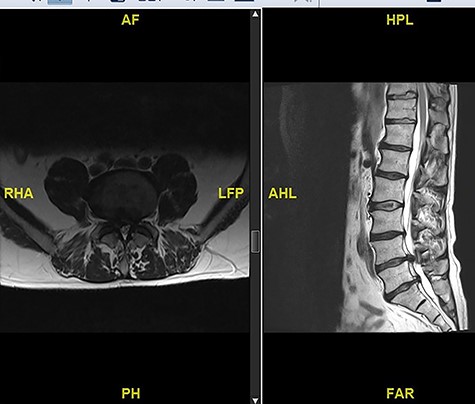

A 56-year-old male patient lumber decompression in a local neurosurgical centre for severe canal stenosis at L1/2 and L2/3 (Fig. 1) level after presenting with bilateral leg weakness and perianal numbness. Three months later he presented with recurrence of right leg pain radiating into the calf and worsening back pain as well as distal lower limbs weakness bilaterally with no sphincter problem. Following an magnetic resonance induction (MRI), which revealed a disc prolapse at L1/2 (Fig. 2), the patient was referred to our Centre. The images were reviewed by a consultant radiologist and as a possibly of intradural herniated disc disease was described. Intraoperatively no extradural disc prolapse was found, so midline durotomy was performed. Intradural disc herniation (IDH) was identified, which was communicating with the disc space through a midline defect in anterior dura (Fig. 3). This was removed extracted under the microscope. Post-operatively, he had a CSF leak needing re-suturing of dura. The patient did make a good post-operative recovery with no major sensory or motor deficits or sphincter disturbance.

MRI image revealing a recurrence of a disc prolapse, suspected to be an intradural disc at L1/2, confirmed intraoperatively.